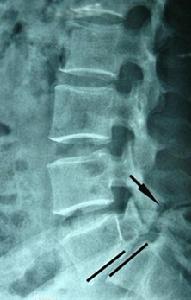

二、側位X片

能清楚顯示椎弓崩裂形態。裂隙於椎弓根後下方,在上關節突與下關節突之間,邊緣常有硬化徵象。側位片可顯示腰椎滑脫徵象,並能測量滑脫分度。國內常用的是Meyerding分級,即將下位椎體上緣分為4等份,根據椎體相對下位椎體向前滑移的程度分為I-IV度。

Ⅰ:指椎體向前滑動不超過椎體中部矢狀徑的1/4者。

Ⅱ:超過1/4,但不超過2/4者。

Ⅲ:超過2/4,但不超過3/4者。

Ⅳ:超過椎體矢狀徑的3/4者。